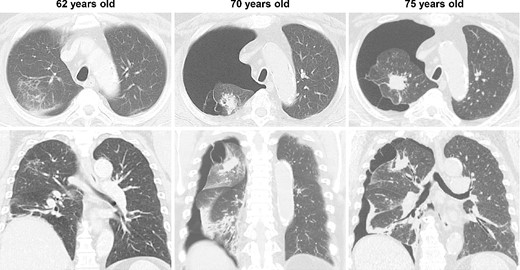

During the computed tomography (CT) scan of the 62-year-old patient, physicians did not point out infiltrating shadows in the right upper lobe caused by suspected pulmonary tuberculosis. Therefore, a chest CT scan was not performed until the patient developed a right pneumothorax at age 70. At 70 years old, the patient developed pneumothorax in his right lung; a CT scan revealed a 3.2 cm mass with satellite lesions in the right upper lobe, as well as pulmonary cysts on the peripheral side of the mass (Fig. 1). At this point, a retrospective review of the patient’s earlier CT images (at age 62 years) confirmed that there were some shadows indicative of pulmonary infiltration in the upper lobe of the right lung, although pulmonary cysts were not visible. The pulmonary cysts were considered to have caused the patient’s pneumothorax, which resolved following chest drainage. A bronchoscopy was performed after the pneumothorax improved, with brushing cytology and bronchoalveolar lavage cytology revealing no malignant cells. An acid-fast bacilli culture of the patient’s bronchoalveolar lavage fluid and the T-cell spot test for tuberculosis infection (T-SPOT.TB) were both negative. An 18F-fluorodeoxyglucose positron emission tomography/CT scan showed a maximum standard uptake value (SUVmax) of 1.8 in the lung mass. Since the lung mass was not suspected to be aggressively malignant [8], careful follow-up was performed, involving another CT scan. The lung mass was not enlarged; however, some growth of the pulmonary cysts was observed (Fig. 2).

CT imaging findings; at age 62, shadows suggesting pulmonary infiltration were present in the upper lobe of the patient’s right lung, but no pulmonary cysts were observed; at age 70, the patient developed spontaneous pneumothorax in his right lung; another scan revealed a 3.2 cm lung mass with satellite lesions in the upper lobe of the right lung, as well as pulmonary cysts on the peripheral side of the mass; at age 75, the patient experienced a relapse of the spontaneous pneumothorax in the same lung.

At 75 years old, the patient’s right spontaneous pneumothorax relapsed (Fig. 1). Exploratory surgery was performed to diagnose the lung mass and treat the pneumothorax. The lung mass and pulmonary cysts were excised (Fig. 3A and B). The lung mass was diagnosed as a granuloma with necrosis through analysis of frozen surgical biopsy sections, and a polymerase chain reaction (PCR) test for tuberculosis was positive. The operative time was 134 min, and the estimated blood loss was 15 ml. No postoperative air leakage was observed, and the patient’s chest drain tube was removed on postoperative Day 2. He was discharged on postoperative Day 12, following respiratory rehabilitation due to his obesity. The timeline of the patient’s clinical course is presented in Fig. 4.